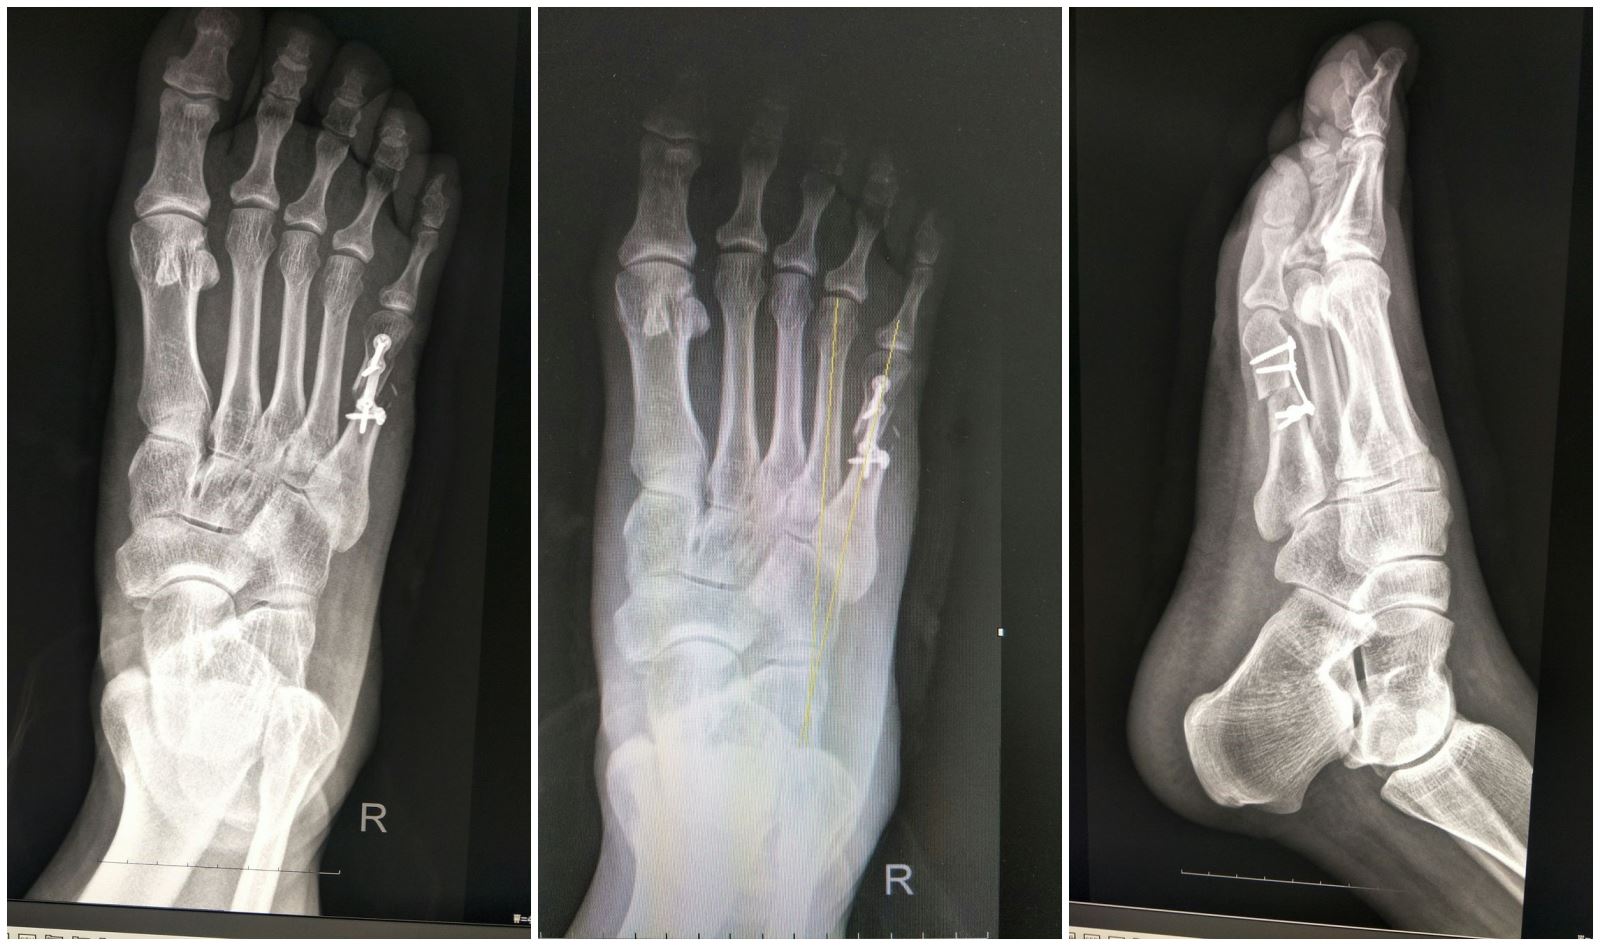

2018 8 18 5 WEIL

4 5 4 5 7° 5